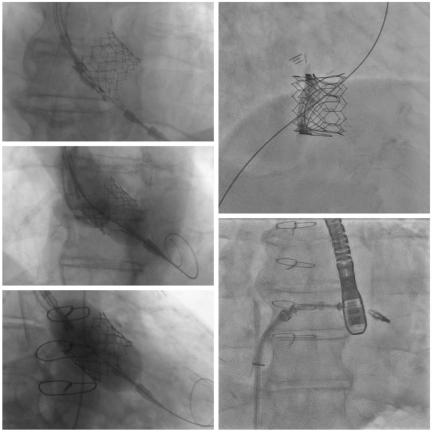

Experto en cateterismo cardíaco, implantes de stents y precedimientos valvulares percutáneos por mínima invasión (sin cirugía abierta) con cer ficaciones internacionales de implantador de válvula aór ca transcatéter (TAVI).

*Experto en Implante de válvula aór ca transcatéter (TAVI) con cer ficados internacionales de implantador de válvulas TAVI.*

• Remplazo y reparación de válvula mitral y tricúspide transcatéter (Clip Mitral y Tricúspide).

• Cierre de orejuela izquierda / Reparación de fugas paravalvulares.

• Cierre de comunicación interauricular (CIA), interventricular (CIV) y Foramen Ovale Permeable (FOP).

• Cateterismo cardíaco, angioplas a coronaria con implante de stents.